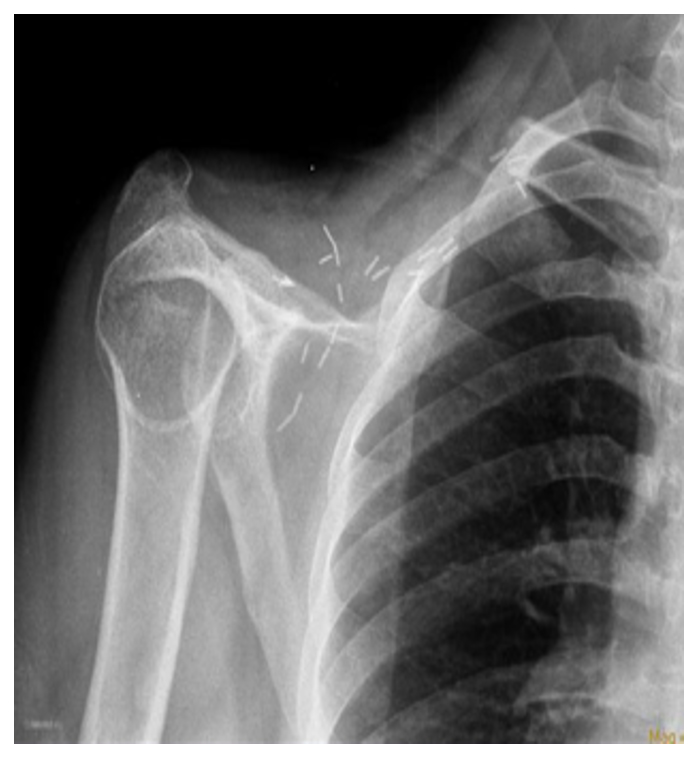

Vaka 04: Köprücük Kemiği (Klavikula) Yerleşimli Kondrosarkom

Genç erkek hasta, köprücük kemiği bölgesinde şişlik, ağrı ve hareket kısıtlılığı şikayetleri ile başvurmuş; biyopsi sonucunda kondrosarkom tanısı doğrulanmıştır. Yapılan değerlendirmelerde cerrahi için uygun bulunmuştur.

Ameliyat Öncesi: Röntgen ve tomografide klavikula üzerinde düzensiz sınırlı kıkırdak dokusu içeren tümör dokusu görülmekte.